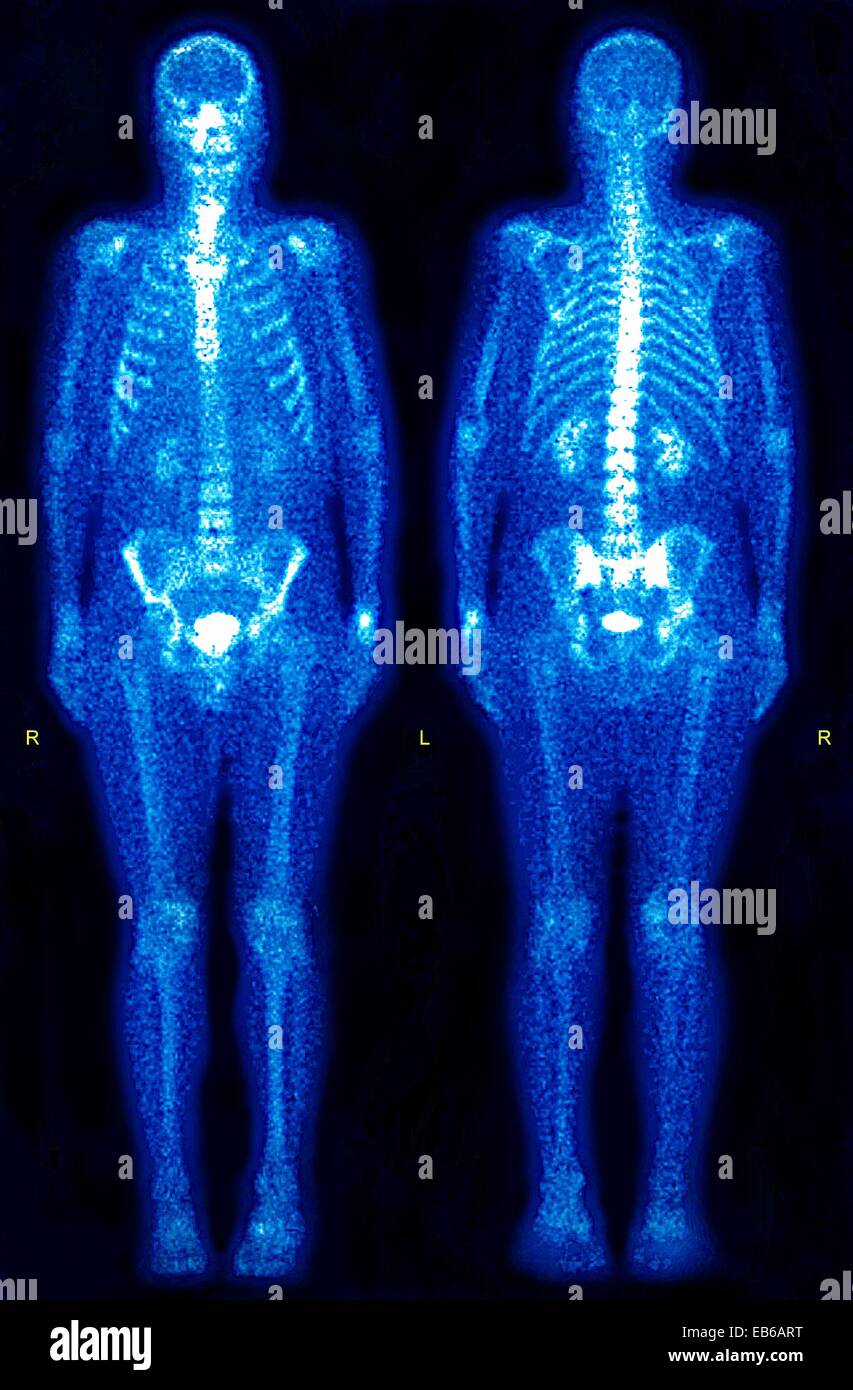

What Are Radioactive Tracers In Medicine . What’s a nuclear medicine scan? This branch of radiology is often. Nuclear medicine is a specialized area of radiology that uses very small amounts of radioactive materials to examine organ function and structure. To make soft tissues, such as blood vessels or the kidneys, show up through medical imaging processes. The images are digitally generated on a computer and transferred to a nuclear medicine physician, who interprets the images. Nuclear medicine is a medical specialty that uses radioactive tracers (radiopharmaceuticals) to assess bodily functions and to diagnose and. A nuclear medicine scan uses small amounts of radiation to create pictures of tissues, bones,. Nuclear medicine is a medical specialty that uses radioactive tracers (radiopharmaceuticals) to assess bodily functions and to diagnose and. Radioactive tracers have transformed the landscape of medical diagnostics through their unique ability to provide functional insights into.

What Are Radioactive Tracers In Medicine Nuclear medicine is a specialized area of radiology that uses very small amounts of radioactive materials to examine organ function and structure. The images are digitally generated on a computer and transferred to a nuclear medicine physician, who interprets the images. To make soft tissues, such as blood vessels or the kidneys, show up through medical imaging processes. A nuclear medicine scan uses small amounts of radiation to create pictures of tissues, bones,. Nuclear medicine is a medical specialty that uses radioactive tracers (radiopharmaceuticals) to assess bodily functions and to diagnose and. Nuclear medicine is a specialized area of radiology that uses very small amounts of radioactive materials to examine organ function and structure. Radioactive tracers have transformed the landscape of medical diagnostics through their unique ability to provide functional insights into. What’s a nuclear medicine scan? This branch of radiology is often. Nuclear medicine is a medical specialty that uses radioactive tracers (radiopharmaceuticals) to assess bodily functions and to diagnose and.

Radioactive tracer hires stock photography and images Alamy What Are Radioactive Tracers In Medicine This branch of radiology is often. A nuclear medicine scan uses small amounts of radiation to create pictures of tissues, bones,. Nuclear medicine is a medical specialty that uses radioactive tracers (radiopharmaceuticals) to assess bodily functions and to diagnose and. Nuclear medicine is a specialized area of radiology that uses very small amounts of radioactive materials to examine organ function. What Are Radioactive Tracers In Medicine.